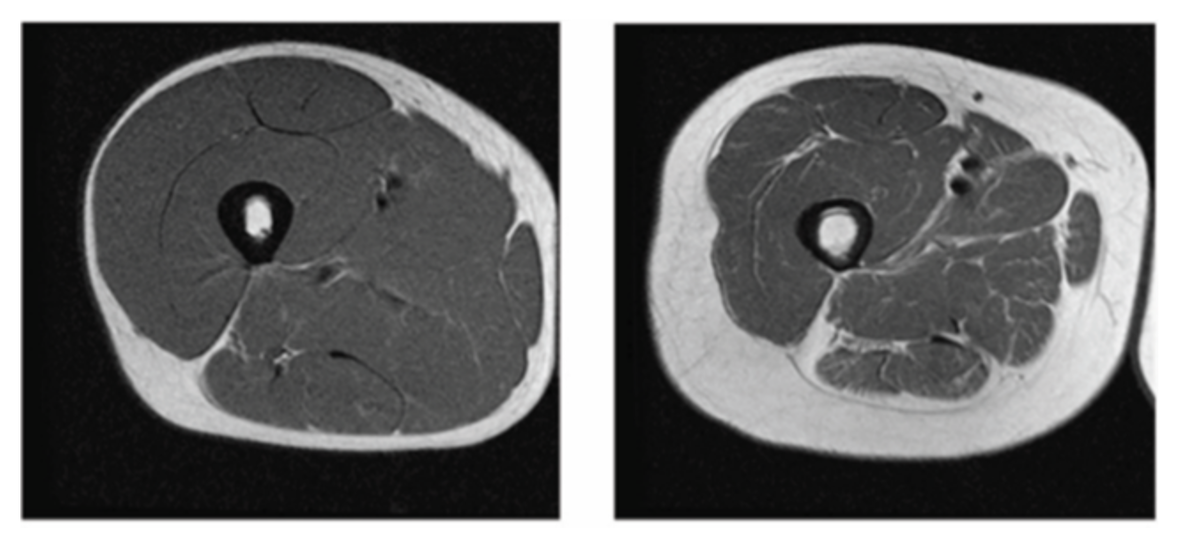

А как это выглядит на снимке КТ, посмотрите слева здоровый срез - темное - это мышцы живые, а светлое это фиброзная и жировая ткань. Оцените пропорции. Справа - клинически проявленная жировая саркопения (по центру кость). Объем при этом в сантиметрах был бы одинаков, а по весу правый даже легче левого.

Слева здоровый человек, справа уже нет